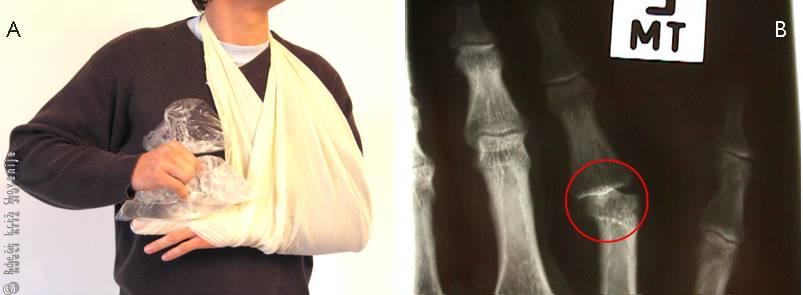

Slika 13

A – Pravilna prva pomoč pri sklepnih poškodbah prstov. Odstraniti je potrebno ves nakit s prstov, poškodovani prst imobilizirati, dvigniti ter hladiti.

B – Na rentgenski sliki je viden delni izpah (subluksacija) bližnjega sklepa med členki.